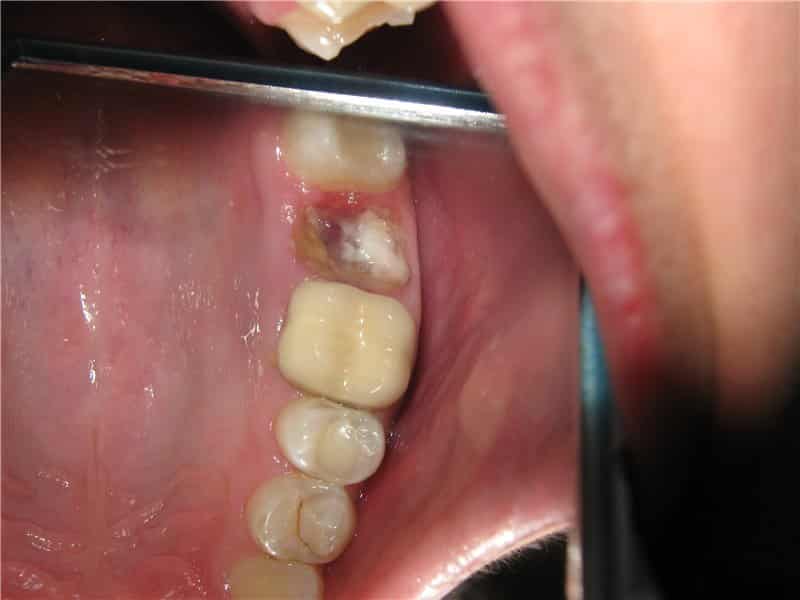

Что делать, если после удаления зуба лунка остается сухой (см. фото)? Какие могут быть причины этого явления и является ли это признаком альвеолита? Существует несколько ключевых факторов, способствующих развитию альвеолита в лунке:

- лунка выглядит пустой и сухой, отсутствует защитный кровяной сгусток, десна вокруг лунки сильно воспалена и вызывает боль при нажатии;

Если кровяной сгусток не образуется, то через несколько дней может возникнуть тупая ноющая боль, часто охватывающая одну из сторон челюсти. Обычно в лунке нет крови и гноя, что позволяет увидеть костную ткань.

Также стоит незамедлительно обратиться к врачу, если после удаления зуба сгусток выпал из лунки. Только стоматолог может правильно лечить альвеолит (см. фото). Задержка в обращении за медицинской помощью может привести к остеомиелиту и даже к серьезным последствиям.